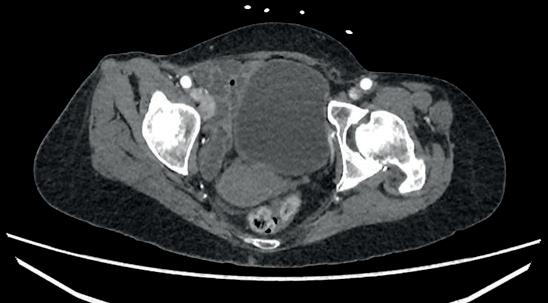

PeVD occurs when enlarged veins develop in the pelvis surrounding the uterus or ovaries, which can lead to severe chronic pelvic pain. Speaking to Interventional News, SIR Foundation chair and member of The VIVA Foundation board of directors Maureen P Kohi (The University of North Carolina, Chapel Hill, USA) referenced a call to action from the World Health Organization (WHO), which looked at global data citing pelvic pain as a central manifestation of the disease in women.

“The main treatment that we’ve been offering is OVE, and we know that the

data show a substantial improvement in chronic pain, but we’ve not been able to produce high-quality evidence to support that treatment option. Not only for the scientific community but also to our payers. Many women do not have insurance coverage for this procedure,” said Kohi. In women, these veins can be difficult to see and feel, Neil Mansho Khilnani (Weill Cornell Medicine, New York, USA)—a member of the EMBOLIZE steering committee—explained, which has driven “scepticism” over diagnosing and treating the pain. “The payers also hear this scepticism and jump on that as an opportunity to reduce expenses to their budget.”

scores on a visual analogue scale from four weeks before treatment through six months post-treatment to evaluate the outcome of vein-directed intervention for venous-origin chronic pelvic pain. Investigators will also evaluate other quality-of-life improvements, improvements in the pelvic vein varices, and changes in pain medication usage.